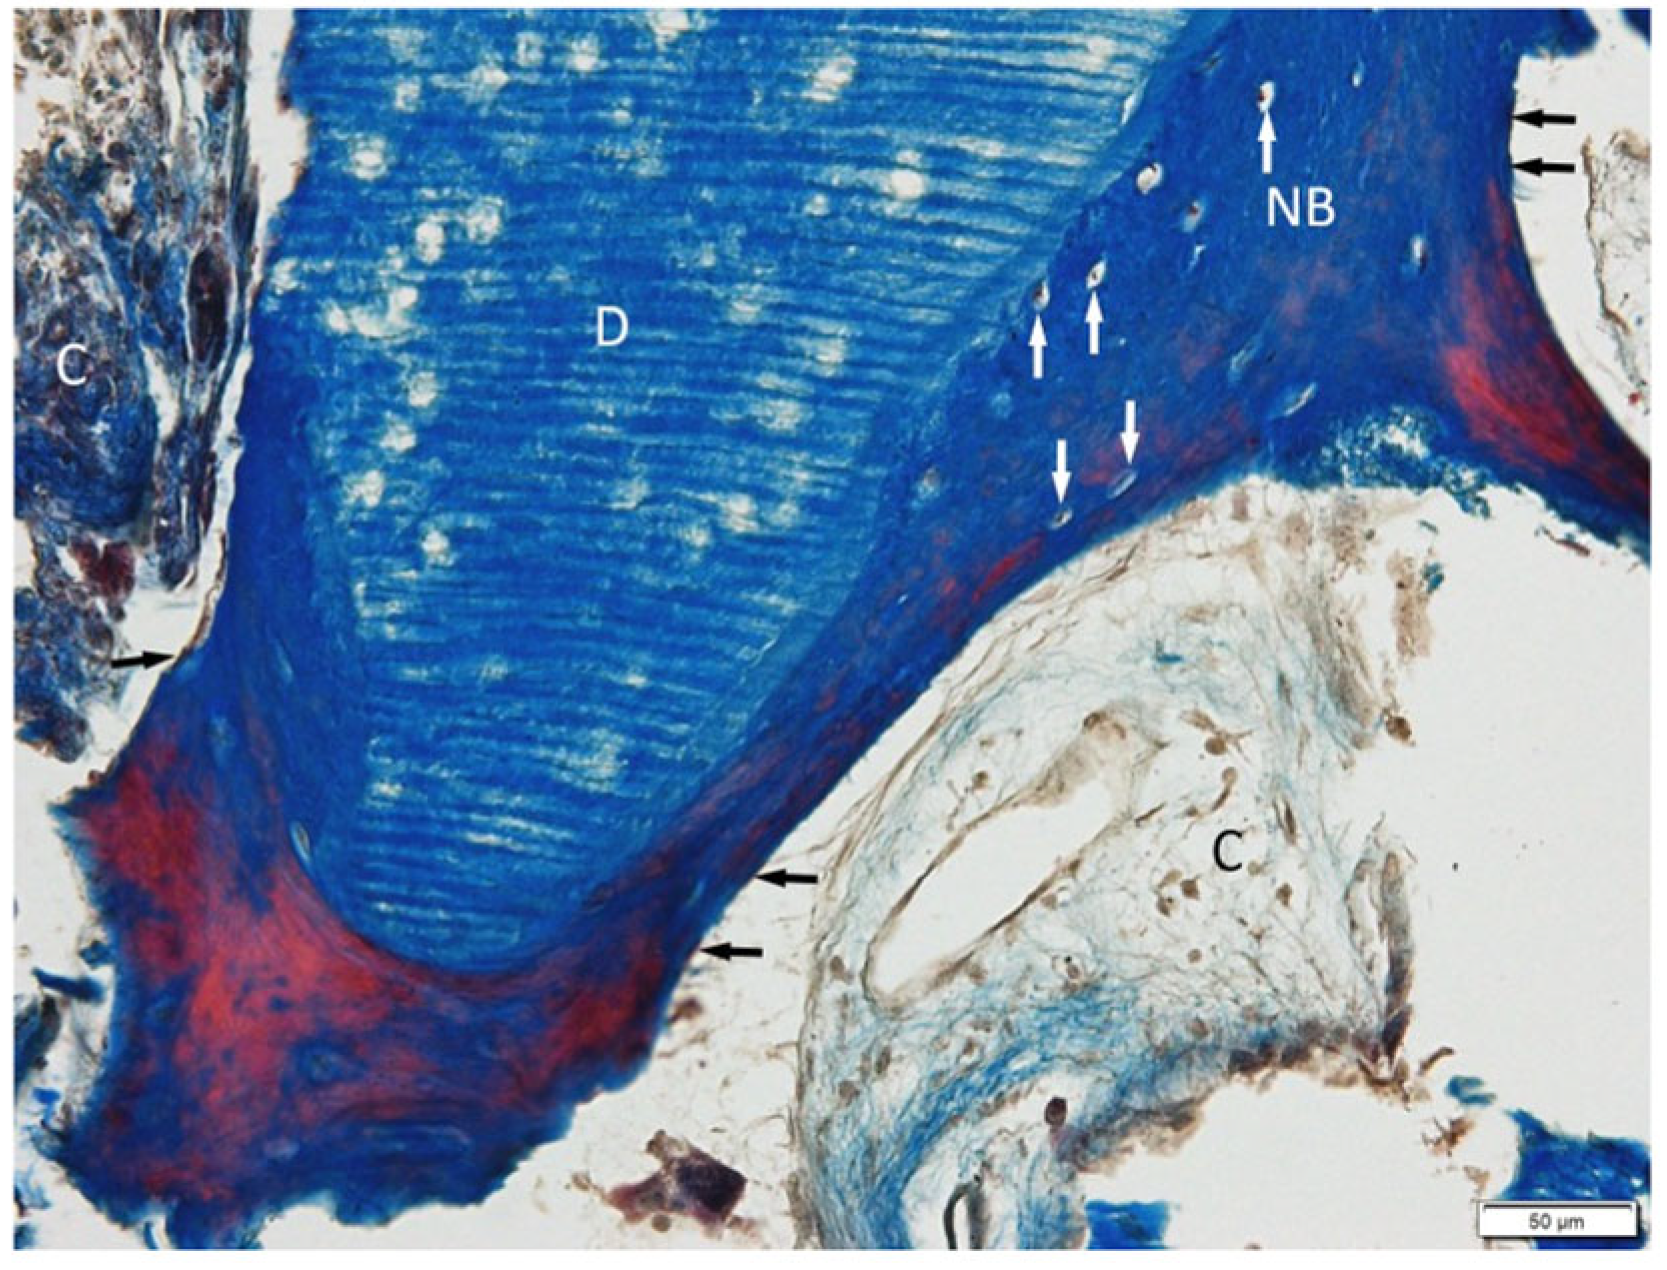

3.1. Histological Examination

3.1.1. BonMaker ST

3.1.2. Smart Dentin Grinder ST

3.1.3. Bio-Gen Mix Xenograft SB

3.1.4. BioBank Allograft SB

3.2. Histological Evaluation of Graft Integration with Bone Tissue